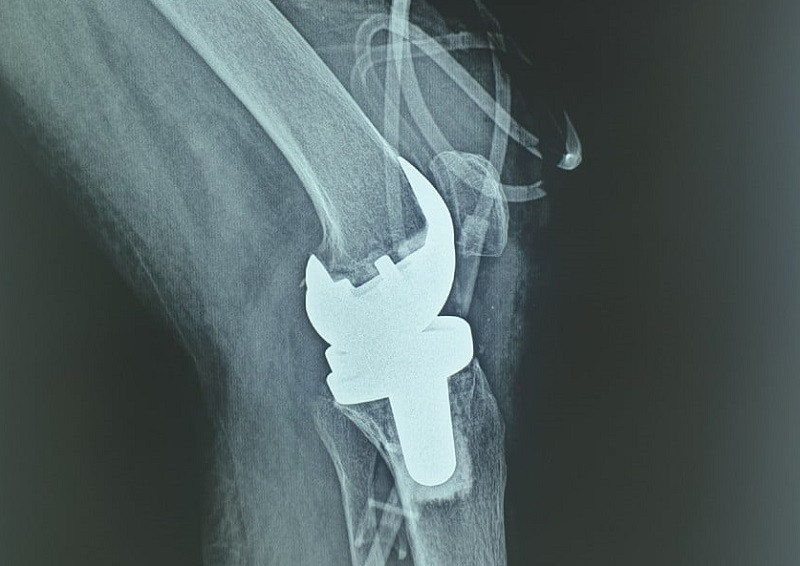

Bệnh viện Phổi Trung ương đã triển khai thành công ca phẫu thuật thay khớp gối nhân tạo cho người bệnh 59 tuổi bị mắc lao khớp gối. Đây là trường hợp người bệnh bị lao khớp gối đầu tiên tại Việt Nam được phẫu thuật thay khớp gối nhân tạo thành công.

Các bác sĩ đã hội chẩn, quyết định thực hiện phẫu thuật làm sạch khớp gối, song song với điều trị đa hóa trị liệu. Tháng 3-2021, người bệnh nhập viện theo hẹn khám lại, sau khi thăm khám và thực hiện các xét nghiệm thấy tình trạng viêm giảm nhiều, chụp phim đánh giá không còn áp xe khớp gối nữa, các bác sĩ khoa Ngoại tổng hợp quyết định phải tiến hành phẫu thuật thay khớp gối nhằm giúp cho người bệnh có cơ hội trở lại sinh hoạt bình thường.

TS, BS Nguyễn Khắc Tráng – Trưởng khoa Ngoại tổng hợp, Bệnh viện Phổi Trung ương cho biết, phẫu thuật thay khớp gối bằng khớp nhân tạo là một phương pháp tiên tiến giúp bệnh nhân phục hồi gần như hoàn toàn chức năng vận động của khớp. Chỉ định thay khớp gối nhân tạo đa số do thoái hóa khớp, ngoài ra còn chỉ định trong trường hợp chấn thương làm hỏng khớp, các bệnh lý viêm khớp – màng hoạt dịch làm hỏng sụn khớp.